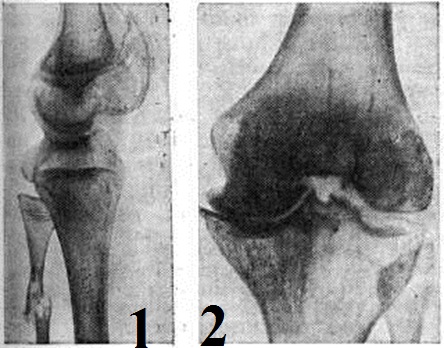

У женщин-носителей патологический гена обнаруживают иногда незначительную кровоточивость и уменьшение содержания фактора VIII или IX. У женщин Гемофилия возникает только при наличии двух поражённых Х-хромосом: от больного Гемофилия отца и от матери носителя патологический гена. Описано 24 достоверных случая Гемофилия у женщин [Уинтроб (М. Wintrobe), 1967]. Следовательно, гипотеза Бауэра (К. Н. Bauer, 1922) об отсутствии потомства от больного Гемофилия мужчины и женщины-носителя патологический гена вследствие формирования так наз. летального гена не получила подтверждения. С помощью клинико-генетических исследований различают наследственную, семейную и спонтанную (спорадическую) форму Гемофилия; последняя является следствием вновь возникших мутаций и составляет около 28% для гемофилии А и 9% для гемофилии В. При гемофилии обнаруживают также сопряжённое нарушение функции близлежащих в X хромосоме генов: глюкозо-6-фосфатдегидрогеназы, цветовой слепоты и другие. Патогенез связан с нарушениями в первой фазе свёртывания крови вследствие недостатка продукции факторов VIII или IX, которые участвуют в образовании тромбопластина. При Гемофилия нарушен внутренний механизм образования тромбопластина, что проявляется удлинением времени свёртывания крови. Фактор VIII является гликопротеидом, содержится в плазме, концентрация его у здоровых людей составляет 10 миллиграмм/литров. Структура фактора окончательно не установлена. Фактор VIII быстро разрушается при консервировании крови и нагревании. В процессе свёртывания фактор VIII потребляется и поэтому в сыворотке не содержится. При фракционировании плазмы по методу Кона фактор VIII выделяется с I фракцией. Предполагаемое место синтеза — печень, селезёнка, лейкоциты. Период полураспада 6—8 часов. Фактор IX — белок плазмы и сыворотки — относится к группе β2-глобулинов, молекулярный вес около 80 000, стабилен при консервировании крови и нагревании. Из плазмы адсорбируется с помощью BaSO4, Al(ОН)3 и другие. В процессе свёртывания не потребляется и потому содержится в сыворотке. При фракционировании плазмы по методу Кона выделяется с фракциями III и IV. Период полураспада — 24 часа. Патологическая анатомияИзменения во внутренних органах, костно-суставной системе и так далее являются следствием массивных кровотечений и кровоизлияний (ишемия органов, изменения в костях, суставах, мышцах в результате образования осумкованных, оссифицированных гематом, кист и другие). В межмышечных гематомах быстро (включается внешний механизм свёртывания) образуются сгустки. Такие гематомы плохо рассасываются и в дальнейшем подвергаются организации, а при повторных кровоизлияниях образуются псевдоопухоли, достигающие больших размеров. Повторные кровоизлияния в суставы являются причиной нарушения их функции. Клиническая картина гемофилии А и гемофилии В характеризуется кровоточивостью. Кровотечения возникают периодически, как правило, через 1 — 2 часа после травмы, причём травма может быть ничтожной, а кровотечение обильным. У некоторых больных выявляют цикличность таких кровотечений, нередко зависимых и от времени года. Кровотечения могут иметь различную локализацию, чаще кровь изливается в мягкие ткани и суставы. Наружные кровотечения возникают после перерезки пуповины, при прорезывании или экстракции зубов, после травм и оперативных вмешательств. Внутренние кровотечения могут быть забрюшинные, в органы грудной и брюшной полости, центральной нервной системы. Симптомы Гемофилия могут проявляться в момент рождения (кефалогематомы, кровотечения из пупочной ранки). С возрастом локализация кровотечения меняется. Если на первом году жизни у детей более часты кровотечения из слизистых оболочек носа и ротовой полости (вследствие прикуса языка, ранения щек, прорезывания молочных зубов), кровоизлияния под кожу и подкожную клетчатку, то у 2—3-летних детей обнаруживаются кровоизлияния в суставы и мягкие ткани. У детей 7—9 лет наряду с гемартрозами (смотри) нередко наблюдаются кровотечения из дёсен при смене зубов, гематурия (смотри) и кровоизлияния во внутренние органы. Периоды ремиссии у больных Гемофилия детей короче, чем у взрослых. Тяжесть клинической, течения не зависит от формы Гемофилия (А или В), а определяется уровнем дефицитного фактора. Гемофилия протекает с периодами относительного благополучия, неодинаковыми у нескольких членов одной семьи. Различают три формы клинической, течения Гемофилия: тяжелит, среднюю и лёгкую. Многие авторы выделяют четвертую форму — скрытую. Для тяжёлой формы Гемофилия характерно раннее проявление кровоточивости и осложнений (остеоартрозы, контрактуры и так далее). Уровень дефицитного фактора у этих больных составляет до 3% от нормы. Для средней и лёгкой формы Гемофилия характерно более позднее появление кровоточивости. Содержание дефицитного фактора до 4—6% от нормы. Скрытую форму Гемофилия (уровень фактора VIII 6—10%) обычно выявляют случайно или при проведении семейных исследований у больных, у которых обнаруживают избыточную кровоточивость после травм, при экстракции зубов, тонзиллэктомии и других хирургических вмешательствах. Для тяжёлой формы Гемофилия характерны кровоизлияния в суставы, причём обычно суставы поражаются в 2 — 3-летнем возрасте. Гемартроз сопровождается болевыми ощущениями, припуханием, защитной контрактурой мышц, местным и общим повышением температуры. Продолжающееся кровотечение вызывает перерастяжение тканей с последующим некрозом их и вскрытием гематомы. Нередки кровоизлияния в поясничные мышцы, в полость брюшины. Кишечные кровоизлияния протекают с развитием симптомов острого живота. Почечные кровотечения могут проявляться почечной коликой. При упорных кровотечениях из желудочно-кишечного тракта нередко развивается тяжёлая анемия. У больных Гемофилия возникают обильные кровотечения после удаления зубов (описаны случаи смертельных кровотечений). Чрезвычайно опасны для жизни больного кровоизлияния в головной мозг, мозжечок, мозговые оболочки, спинной мозг. ОсложненияПри Гемофилия лёгкой и средней тяжести осложнения возникают редко. Повторные кровоизлияния в сустав вызывают утолщение капсулы, узурирование хряща и остеопороз. При кровоизлияниях в коленный сустав, который поражается чаще, кровь скапливается в верхнем завороте, вызывая резкие боли и вторичную рефлекторную атрофию четырёхглавой мышцы. При отсутствии лечения развивается стойкая контрактура. Характерно образование кровяных кист в метафизе, реже в диафизе трубчатых костей. Иногда кисты локализуются в тазовых, пяточных костях. Наличие деструктивных процессов в костях нередко приводит к патологический переломам (рисунок 1). При обширных подкожных, внутримышечных, забрюшинных кровотечениях может наступить сдавление сосудов и нервов с последующим развитием некрозов, параличей и ишемической контрактуры. Локализация значительных по размеру псевдоопухолей и геморрагических кист в брюшной полости может симулировать картину кишечной непроходимости. Забрюшинная локализация их может вести к сдавлению мочеточников. При локализации гематом по ходу магистральных сосудов и нервных стволов возможно сдавление их, что ведёт к развитию параличей, ишемии органов, гангрены конечностей и другие. Гематурия при Гемофилия нередко ведёт к образованию сгустков в мочевыводящих путях (особенно на фоне антифибринолитической терапии) с окклюзией мочевыводящих путей и нарушением функций почек. Диагноз основывается на данных анамнеза, клин, картины и лабораторных исследований. Важное значение имеет тщательный сбор анамнеза (кровоточивость у мужчин в семье по линии матери, кровотечения с преимущественным поражением суставов, связанные с предшествующей травмой, их длительность и рецидивы). При осмотре больных обращают внимание на наличие кровоизлияний, гематом, изменения в суставах. При коагулологическом исследовании крови (смотри Коагулограмма) наличие у больного Гемофилия можно заподозрить на основании удлинения времени свёртывания крови (смотри) и времени рекальцификации плазмы, снижения потребления протромбина, что указывает на нарушение тромбопластинообразования. Характерны изменения тромбоэластограммы (смотри Тромбоэластография). Но окончательный диагноз Гемофилия ставят по результатам исследования парциального тромбопластинового времени и теста генерации тромбопластина по Биггс — Дугласу. При гемофилии А этот тест корригируется добавлением плазмы, адсорбированной BaSO4 или Al(ОН)3; при гемофилии В — добавлением сыворотки. Однако и он является недостаточно чувствительным. Наиболее точная диагностика основывается на количественном определении факторов VIII и IX. Дифференциальный диагнозНекоторые симптомы, характерные для Гемофилия, наблюдаются и при других заболеваниях. При ангиогемофилии (смотри) кровоточивость встречается у лиц обоего пола, чаще у женщин; выявляется чрезмерное удлинение времени кровотечения (смотри); кроме дефицита фактора VIII, в крови уменьшено содержание сосудистого фактора. При болезни Стюарта — Прауэр (смотри Геморрагические диатезы) кровоточивость (преимущественно у женщин молодого возраста) обусловлена дефицитом фактора X. Одновременно с нарушением первой фазы свёртывания крови выявляют нарушение парциального тромбопластинового времени и уменьшение протромбинового индекса (смотри Протромбиновое время). При коллагенозах, туберкулёзе, злокачественных новообразованиях, воздействии ионизирующей радиации, медикаментозных и других интоксикациях в крови появляются циркулирующие антикоагулянты, чаще к фактору VIII, имитирующие клинику Гемофилия При дифференциации их с Гемофилия большое значение имеют данные анамнеза: отсутствие указаний на кровоточивость у других членов семьи, появление первых признаков кровоточивости в зрелом возрасте на фоне возникшего заболевания. Важными для дифференциального диагноза тестами являются так называемый. Перекрёстные пробы: добавление к исследуемой крови или плазме 0,1 объёма крови или плазмы здорового человека нормализует время свёртывания крови у больных Гемофилия; при наличии в крови любого антикоагулянта проба отрицательна. Наоборот, добавление 0,1 объёма крови с антикоагулянтом к нормальной крови увеличивает время её свёртывания. Дополнительными исследованиями являются проба Биггс — Бидуэлл на антитела к фактору VIII, определение содержания свободного гепарина и титрование с протаминсульфатом. При иммуноэлектрофоретическом исследовании со специфическими антисыворотками к фактору VIII (IX) выявляется типичная дуга преципитации; количественное определение антикоагулянта проводят методом радиальной иммунодиффузии. Рентгенодиагностика изменений костей и: суставов характеризуется признаками поражения опорно-двигательного аппарата вследствие кровоизлияний в полости суставов, в костномозговые пространства и в мягкие ткани. Однократные кровоизлияния в суставы могут быстро и бесследно рассасываться. В острый период гемартроза рентгенологическое. Картина не специфична. На рентгенограммах иногда обнаруживается небольшое расширение суставной щели, обусловленное скоплением крови. Повторные кровоизлияния в суставы приводят к гемофилическому остеоартрозу. Рентгенологическим признаком повторных кровоизлияний, начавшихся в детском возрасте, является изменение размеров и формы сустава. Рентгенологически различают четыре стадии гемофилического остеоартроза. На рентгенограммах в I стадии обнаруживают остеопороз суставных концов и утолщение суставной капсулы. II стадия характеризуется уменьшением объёма движений в суставе за счёт утолщения капсулы и образования внутри сустава организующихся гематом. В III стадии выявляют сужение суставной щели и изменение конфигурации суставных концов костей вследствие разрушения подхрящевых отделов эпифизов, костных разрастаний (рисунок 2), кистовидной перестройки эпифизов. В IV стадии суставная щель на рентгенограммах не видна или резко сужена. Подхрящевые отделы эпифизов значительно склерозированы. Имеются некоторые особенности в рентгенологическое картине различных суставов с гемофилическим остеоартрозом: в коленном суставе часто разрушаются межмыщелковая ямка бедра, боковые поверхности мыщелков и надколенник; в локтевом — полулунная выемка локтевой кости; в плечевом — вдоль анатомической шейки образуются краевые узуры, иногда напоминающие сухую костоеду; в тазобедренном — развивается остеохондропатия. При внутрикостных кровоизлияниях крупные кистозные полости обнаруживаются чаще в эпифизах, но встречаются и в диафизах. Организующаяся гематома рентгенологически может дать картину так называемый гемофилической псевдоопухоли кости (рисунок 3). При формировании геморрагических кист в прилежащих отделах скелета обнаруживаются атрофические процессы с почти полным рассасыванием обширных участков кости. По краям кист выявляются экзостозные костные образования, свидетельствующие о репаративных процессах в костной ткани. В области дефекта кости можно видеть костные и известковые включения, которые при дефекте, расположенном в краевом отделе кости, могут дать картину «козырька» (рисунок 4), как при остеогенной саркоме. При Гемофилия могут наблюдаться также внутрикостные очаги склероза, субпериостальные оссифицированные гематомы, параоссальные оссификаты. Почти у половины больных выявляют оссифицирующие гематомы в мягких тканях. Гемофилия может быть причиной прогрессирующего оссифицирующего миозита. Правильная интерпретация клинико-рентгенологическое симптоматики поражений опорно-двигательного аппарата при Гемофилия позволяет провести дифференциальную диагностику с артрозами и изменениями костей другой этиологии и определить показания к различным видам лечения (хирургическое, ортопедическое, лучевое). ЛечениеОсновным методом лечения больных Гемофилия является возмещение недостающего фактора свёртывания крови. Лечение осложнений, вызванных кровотечениями и кровоизлияниями (гематомы, гемартрозы, контрактуры и так далее), иногда связано с хирургическими вмешательствами. Хирургические вмешательства как по поводу осложнений Гемофилия, так и в связи с заболеваниями, требующими хирургического лечения (аппендицит, непроходимость кишечника, язва желудка, травмы и так далее), имеют свои особенности. Лечение Гемофилия важно начать с первых проявлений кровоточивости. Позднее начало лечения, как правило, приводит к тяжёлым осложнениям и, кроме того, удлиняет курс лечения. Больным назначают цельную кровь, плазму (нативную замороженную, лиофилизированную) и антигемофильные препараты (концентраты факторов VIII и IX), а также ингибиторы фибринолиза. Свежую кровь или плазму необходимо вводить в больших объёмах (до доведения концентрации антигемофильного фактора в крови до требуемого уровня); это ограничивает их применение, так как наибольший объем переливаемой крови и плазмы за 24 часа не должен быть более 25 миллилитров на 1 килограмм веса тела, и повторные инфузии больших объёмов могут привести к перегрузке в системе циркуляции, образованию антител к фактору VIII (или IX), анафилактической и температурной реакции, гематурии, нарушению функции почек и так далее. В антигемофильных препаратах концентрацию фактора VIII (или IX) выражают единицами активности. За 1 единиц активности фактора VIII (или IX) принято его количество, содержащееся в 1 миллилитров нормальной плазмы, полученной при смешивании плазмы от многих доноров. Расчёт дозы антигемофильного препарата производят в единицах активности фактора VIII (или IX). При введении больному 1 единиц антигемофильного препарата на 1 килограмм веса тела уровень фактора VIII повышается на 1—2%. Дозу препарата рассчитывают по исходному уровню дефицитного фактора в крови больного, а также по периоду его полураспада. Период полураспада фактора VIII после однократного введения больному антигемофильного глобулина составляет 6—8 часов, после остановки кровотечения период полураспада удлиняется до 13—26 часов. [Бринкхаус (К. Brinkhous), 1970; Ю. И. Андреев с соавторами, 1972]. Период полураспада фактора IX колеблется от 12 до 24 часов [Биггс (R. Biggs), 1970; Султан (Y. Sultan), 1970]. Концентрированные препараты вводят внутривенно, струйно, с помощью шприца или системы для переливания крови. Методы приготовления антигемофильных препаратов. При хранении консервированной крови и плазмы при плюсовой температуре фактор VIII инактивируется в течение нескольких часов. Поэтому свежую плазму, быстро отделённую от эритроцитов, замораживают при t° —25—40°. Эту плазму готовят следующим образом. Кровь от донора набирают в пластмассовый мешок (один из двух спаренных) с консервантом. Оба мешка (с пережатой соединительной трубкой между ними) центрифугируют 20 минут. Затем слой плазмы перемещают во второй мешок путём лёгкой внешней компрессии, герметизируют соединительную трубку, которую затем перерезают. Оставшиеся в первом мешке форменные элементы крови используют для переливания. Полученная плазма используется для переливания или является исходным сырьём для приготовления антигемофильных препаратов: криопреципитата и концентрата фактора VIII. Антигемофильная плазма содержит в 1 миллилитров 0,2—1,6 единиц фактора VIII. Хранят её при t° —30°. Гемостатическая доза — 10 миллилитров на 1 килограмм веса тела. Суточная доза 20 миллилитров на 1 килограмм веса тела. Криопреципитат впервые получен Пул (I. Pool, 1965), широко используется во всем мире. Представляет собой белковый препарат изогенной плазмы человека, в малом объёме содержит от 5 до 15 единиц/миллиметров фактора VIII. Хранится при t° — 30° или в высушенном виде, растворим при t° 35—37°. Применяется с учётом совместимости по АВ0-группам крови. Известны также высокоочищенные лиофилизированные концентраты фактора VIII с активностью до 30—50 единиц/миллилитров. Фактор IX адсорбируют на трикальцийфосфате, гидроокиси алюминия, сернокислом барии и других адсорбентах, на чем основаны методы выделения его. Выбор адсорбента и другие методические особенности приготовления указанных концентратов зависят от вида консерванта, стабилизирующего плазму. Одновременно с фактором IX адсорбируются факторы II, VII и X, вместе составляющие так наз. комплекс PPSB (по первым буквам названий факторов Р-протромбин (II), Р-проконвертин (VII), S — фактор Стюарта, В — антигемофильный фактор IX. Фактор IX устойчив при хранении плазмы при плюсовой температуре и выделение его не требует таких предосторожностей, как при работе с фактором VIII. Протромбиновый комплекс РРSВ впервые получен Ж. Сулье, в СССР — Л. В. Минаковой. При получении комплекса PPSB важно правильно выбрать стабилизатор, предотвращающий свёртывание крови. Первоначальное предложение об использовании с этой целью ионообменных смол не получило применения в промышленных масштабах выделения комплекса PPSB. Использование в качестве стабилизатора лимонной кислоты и её солей резко снижает возможность адсорбции комплекса PPSB из плазмы крови, поскольку цитраты растворяют PPSB с поверхности адсорбентов (например, гидроокиси алюминия). Кроме того, при большом содержании в полученных препаратах цитрата натрия у больных возникают боли. Распространённым стабилизатором крови при получении комплекса PPSB является этилендиаминтетрауксуснокислый натрий (ЭДТА-Na), который имеет, однако, сравнительно высокую токсичность, ограничивающую непосредственное применение PPSB. Метод выделения PPSB заключается в следующем: к плазме добавляют гель трикальцийфосфата (около 5 весовых %) и после перемешивания центрифугируют. Осадок трикальцийфосфата с адсорбированным на нем PPSB дважды обрабатывают 2 — 3% раствором цитрата натрия, отделяя осадок центрифугированием. Центрифугат объединяют и высушивают в замороженном состоянии (лиофилизация). Таким образом, достигают примерно 20-кратной концентрации фактора IX. Превращение протромбина в тромбин предотвращают добавлением гепарина и кофактора гепарина. Возможно выделение PPSB из цитратной плазмы путём адсорбции его на диэтиламиноэтилцеллюлозе с последующим растворением цитратно-фосфатным буфером. Промышленного применения метод пока не имеет. При промышленном получении препарат PPSB выделяют из фракции III Кона. Главная трудность состоит в сложности отделения PPSB от липопротеинов, составляющих основную массу фракции III. Комплекс PPSB содержит в 1 миллилитров 10 — 60 единиц фактора IX. Вводят его после проверки на наличие тромбина. Срок хранения до 1 года. Хранят в лиофилизированном виде при t° 4°. Ингибиторы фибринолиза вводятся с целью угнетения фибринолитических процессов. 5% раствор эпсилонаминокапроновой кислоты вводят внутривенно в дозе до 400 миллилитров в сутки или 4—8 грамм сухого порошка внутрь. Противопоказанием для назначения ингибиторов фибринолиза являются почечные кровотечения. При обширных кровоизлияниях в мягкие ткани, полости, органы, в центральной нервной системы из гемостатических средств предпочтительнее введение концентратов фактора VIII (IX). Вводят гемостатические средства до полной остановки кровотечения. Лечение осложнений гемофилииВажна правильная тактика ведения больных Гемофилия с гемартрозами. При острых гемартрозах необходимо прежде всего снять болевой синдром назначением аналгезирующих средств; однако длительное применение ацетилсалициловой кислоты, бутадиона может усилить кровоточивость, а широкое назначение наркотиков — привести к развитию у больных Гемофилия наркомании. Лечение гемартрозов необходимо начинать в первые часы или сутки от начала кровоизлияния, так как только при этом условии можно рассчитывать на восстановление функции сустава. На фоне трансфузии антигемофильных препаратов аспирируют из полости сустава кровь с последующим введением гидрокортизона и иммобилизацией сустава на 1—2 дня. При хронический гемофилических остеоартрозах в фазе организации гематом в ряде случаев показана местная рентгенотерапия (рисунок 3 и 4). Кроме того, она способствует уплотнению сосудистой стенки. При развитии стойких контрактур с целью их коррекции показаны: липкопластырное вытяжение, этапные гипсовые повязки. При сопутствующем синовите рекомендуется вводить гидрокортизон. При отсутствии эффекта от консервативного лечения (запущенные формы синовита) производится синовэктомия. Операция иссечения синовиальной оболочки сустава способствует восстановлению функции сустава, прекращению повторных кровоизлияний. Операция резекции суставов и корригирующая остеотомия производятся при дегенеративных формах поражения. Пунктирование глубоких межмышечных гематом эффекта не даёт вследствие быстрого свёртывания в них крови; длительно сохраняющаяся гематома является показанием для оперативного опорожнения её на фоне введения антигемофильных препаратов. Обширные гемофилические псевдоопухоли, располагающиеся внутрибрюшинно или вблизи жизненно важных органов, удаляют с полным иссечением их капсулы; подлежат удалению и малые гематомы при появлении признаков их нагноения. Для полной остановки наружного кровотечения вводят 20 единиц антигемофильного препарата на 1 килограмм веса тела, чтобы повысить уровень фактора VIII до 40% от нормы. При желудочно-кишечного кровотечениях лечебный мероприятия должны быть направлены на остановку кровотечения и на ликвидацию анемии. Некупирующиеся при активной гемостатической терапии желудочно-кишечного кровотечения являются показанием для лапаротомии с последующей перевязкой кровоточащего сосуда или, если это невозможно, резекцией органа. Особенности ведения больных гемофилией при хирургических вмешательствах. Всякое хирургическое вмешательство у больных Гемофилия связано с опасностью тяжёлого кровотечения, особенно в послеоперационном периоде. При подготовке больных Гемофилия к хирургическим вмешательствам уровень фактора VIII (или IX) должен быть доведён до 50% от нормы и более. При необходимости, в зависимости от характера предстоящих хирургических вмешательств, содержание дефицитного фактора повышают до 100% и поддерживают этот уровень в течение 3—5 дней. Перед операцией вводят 30—60 единиц антигемофильного препарата на 1 килограмм веса тела. В послеоперационном периоде после больших операций более рационально одномоментно вводить всю суточную дозу препарата либо по 20 единиц на 1 килограмм веса через 8 часов. В течение 10 дней после операции уровень дефицитного фактора необходимо повышать до 30—40% нормы, а затем, в зависимости от состояния, можно переводить больного на профилактические дозы препарата до полного выздоровления. Длительность гемостатической терапии при больших операциях, в том числе и костнопластических, составляет 7—14 дней. Одновременно применяют антифибринолитические средства (5% раствор эпсилон-аминокапроновой кислоты 300—500 миллилитров или 40% раствор ацепрамина 60—80 миллилитров в сутки); кортикостероидные гормоны (преднизолон внутривенно 20—30 миллиграмм, гидрокортизон 50—100 миллиграмм в сутки); сосудоукрепляющие средства (препараты кальция, аскорбиновая кислота, рутин и так далее). При экстракции зубов за 30 минут до операции вводят 30—40 единиц на 1 килограмм веса тела антигемофильного препарата (чтобы повысить уровень дефицитного фактора до 30—40%); повторно препарат вводят через 12 — 24 часа в дозе 10—15 единиц (для поддержания дефицитного фактора не ниже 15—25%). Длительность антигемофильной терапии зависит от характера заживления раны. Прогноз в отношении выздоровления неблагоприятный, однако система диспансеризации и профилактическое введение антигемофильных препаратов значительно улучшают течение заболевания. Заместительная терапия в момент кровотечений позволяет во многих случаях предупредить развитие осложнений, в том числе тяжёлых гемартрозов, и сохранить трудоспособность больных. ПрофилактикаСуществуют активная и пассивная формы профилактики. Активная — систематическое введение препаратов, содержащих факторы VIII и IX, 2 раза в месяц детям с 1 года до 14 лет. Пассивная — своевременное введение удвоенных доз препаратов, содержащих факторы VIII и IX, в момент начавшегося осложнения. Проводится всем больным. Как профилактику Гемофилия можно рассматривать медико-генетическое консультирование мужчины, больного Гемофилия, или женщины-кондуктора (доказанного, возможного или даже потенциального) перед вступлением в брак. Супруги должны быть предупреждены о возможности иметь больного ребёнка (смотри Медико-генетические консультации). Большое значение имеет выявление женщин-кондукторов, что возможно путём количественного определения фактора VIII или IX. Содержание фактора VIII (IX), исследованного различными методами, в крови здоровых женщин оказывается нормальным а у женщин-кондукторов сниженным; биохимический методом выявляется низкий его уровень, а при иммунологический исследовании — высокий. Имеет значение внутриутробное определение пола плода в семьях, где можно предполагать наличие женщин-кондукторов. Для этого предложен метод трансабдоминального амниоцентеза на 14—16-й недель беременности (смотри Амниоцентез). В извлечённой амниотической жидкости изучают плодные клетки для определения Х-хромосомы. Если плод мужского пола, ставят вопрос о прерывании беременности. Больным Гемофилия регулярно вводят концентрированные антигемофильные препараты амбулаторно при гематологические стационаре. Для предупреждения кровотечений и их осложнений профилактическое лечение следует начинать с раннего детского возраста. Даже в тяжёлых случаях Гемофилия кровоточивость непостоянна; это позволяет проводить прерывистый курс лечения с учётом возраста больного и тяжести течения заболевания, что даёт ему возможность сохранить трудоспособность и вести нормальный образ жизни. Профилактическое лечение приводит к повышению исходного уровня дефицитного фактора до значений, характерных для лёгкой формы Гемофилия, способствует более спокойному течению болезни, уменьшает частоту и интенсивность геморрагий. Профилактика осложнений Гемофилия состоит в предупреждении кровотечений и кровоизлияний в суставы и мышцы, что часто является причиной инвалидизации больных. Наиболее эффективно заместительное переливание крови при обострении заболевания или при учащении появления геморрагий. Необходим охранительный режим, особенно для больных Гемофилия детей школьного возраста, так как в этот период особенно часто возникают кровоизлияния в суставы и мышцы. Профилактические и лечебный мероприятия осуществляются гематологические отделениями республиканских, областных и городских многопрофильных больниц. В основу профилактики должно быть положено диспансерное обслуживание больных гемофилией. В задачу диспансерного обслуживания больных Гемофилия входит: учёт и выявление больных Гемофилия, периодическое медицинский и лабораторное обследование их, проведение профилактики и лечение кровотечений и их осложнений. На больного Гемофилия, взятого на диспансерное обслуживание, заполняется специальная карта пробанда (история болезни), содержащая паспортные, краткие анамнестические и генетические сведения, а также данные, отражающие состояние больного: форма Гемофилия, тяжесть течения, групповая и резус-принадлежность крови, наличие в крови антител к клеткам крови, гемограммы, коагулограммы, рентгенограммы суставов и костей. Каждому больному Гемофилия выдаётся «Книжка больного гемофилией», где указывается группа крови, её резус принадлежность, форма Гемофилия, её тяжесть, проводимые лечебно-профилактические мероприятия и рекомендации на случай обострения. Помимо гематологические отделений, лечебно-профилактические работу проводят центры гемофилии на базе институтов гематологии и переливания крови, а также на базе республиканских, областных и городских больниц. Центры гемофилии осуществляют лечебно-профилактические, консультативную, организационно-методическую и научно-исследовательскую работу. Научные исследования направлены на разработку и внедрение в практику лечебный учреждений новых эффективных методов и средств профилактики и лечения больных гемофилией. В некоторых странах для больных Гемофилия детей созданы специальные школы, в которых, кроме общего образования, они получают навыки к посильной профессии. Лечебный гимнастика и физиотерапия в комплексе со специфической терапией укрепляют мышечную и костно-суставную системы, предупреждают рецидивы геморрагий. Смотри также Свёртывающая система крови.